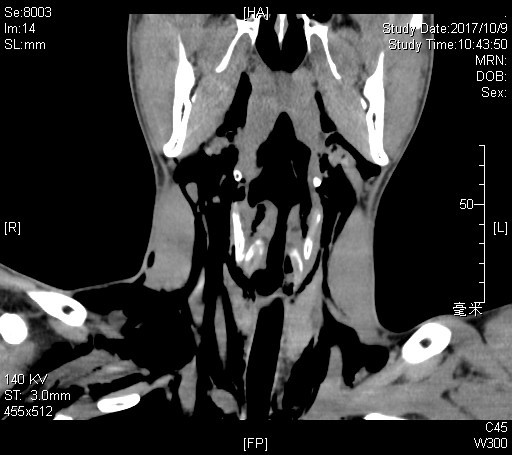

紧接其后,11月中旬,耳鼻咽喉头颈外科门诊迎来一位19岁的患者。小伙子在搬家时脚下一滑摔倒了,脖子不偏不倚卡在了一根金属横梁上。当时颈部并没有明显伤痕,但小伙子感到颈部疼痛难忍,说话声音哑了,还间断咳血;在来医院的路上,脖子越来越粗,而且感到严重的胸闷。接诊的顼晋昆和尹国平主治医师发现患者精神状态变差,呼吸逐渐不畅,颈部皮下有典型的捻发音(极细微而均匀的噼啪音),紧急为患者进行了喉镜检查、颈部CT扫描后,同样诊断为“颈部闭合性外伤、喉气管断裂伤”,气管断裂的位置位于声门下、环状软骨与第一气管软骨环之间。在麻醉科的配合下,耳鼻咽喉头颈外科医师第一时间为患者进行了全麻状态下的“气管切开术+I期喉气管断裂修复术”。术后10天,小伙子没有再出现呼吸困难或进食呛咳,拔除气管套管后康复出院。

图中显示气管断裂、颈部多发皮下气肿